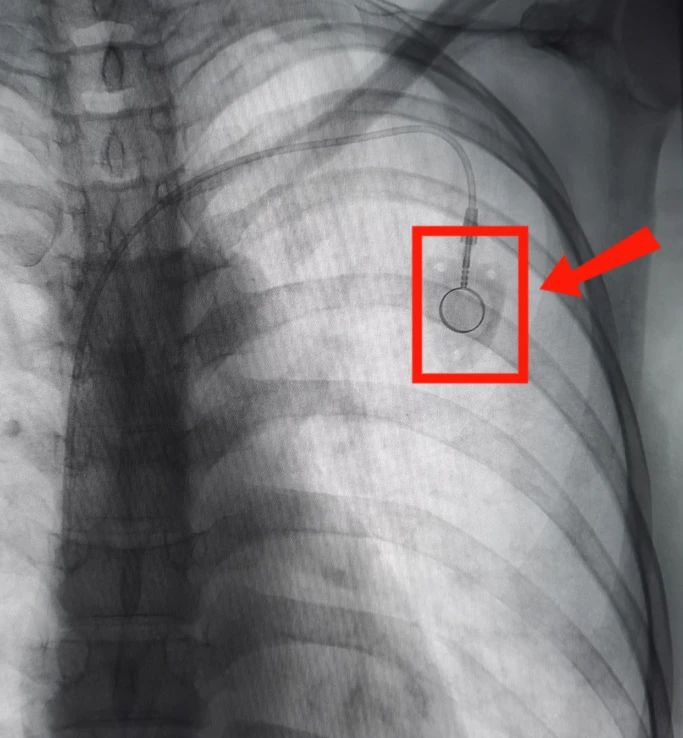

近日,英德市人民医院介入科在刘伟波主任医师的带领下成功为肿瘤患者实施了经腋静脉输液港植入术,帮助患者开通一条安全、长效的“生命线”。该项新技术的成功开展,标志着英德市人民医院静脉输液治疗水平再上新台阶,同时也填补了英德市一项医疗技术空白。

在征得患者及家属的同意后,做好充分准备后,介入科刘伟波主任医师带领医护团队为患者实施了DSA结合超声引导下“经腋静脉输液港植入术”,手术全程仅用时30分钟,患者全程无不适感觉。术后患者恢复良好,顺利完成化疗及免疫治疗后出院。

输液港是一种完全植入人体内的闭合输液装置,是一种完全植入皮下,可长期留置在体内的静脉输液装置,为需要长期静脉输液的患者提供了一种便利、安全、可靠的输液通道。是目前针对化疗病人推荐比较多的一个静脉通道,被患者称为“看不见的生命线”。